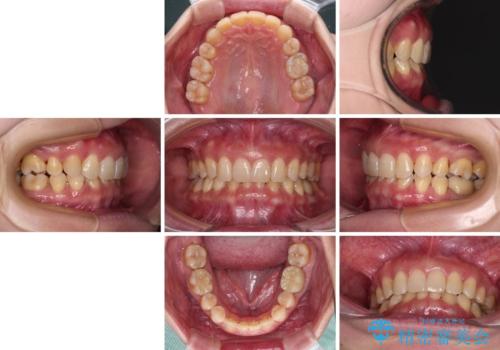

マウスピースでの抜歯矯正特有の抜歯スペースに向かって奥歯が傾斜する動きが顕著に表れ、ディープバイトは改善されませんでした。

前歯のみが強く接触し、奥歯で咬めない期間も続いたため、ワイヤー装置などを補助的に使用し、何とか終了させることができました。